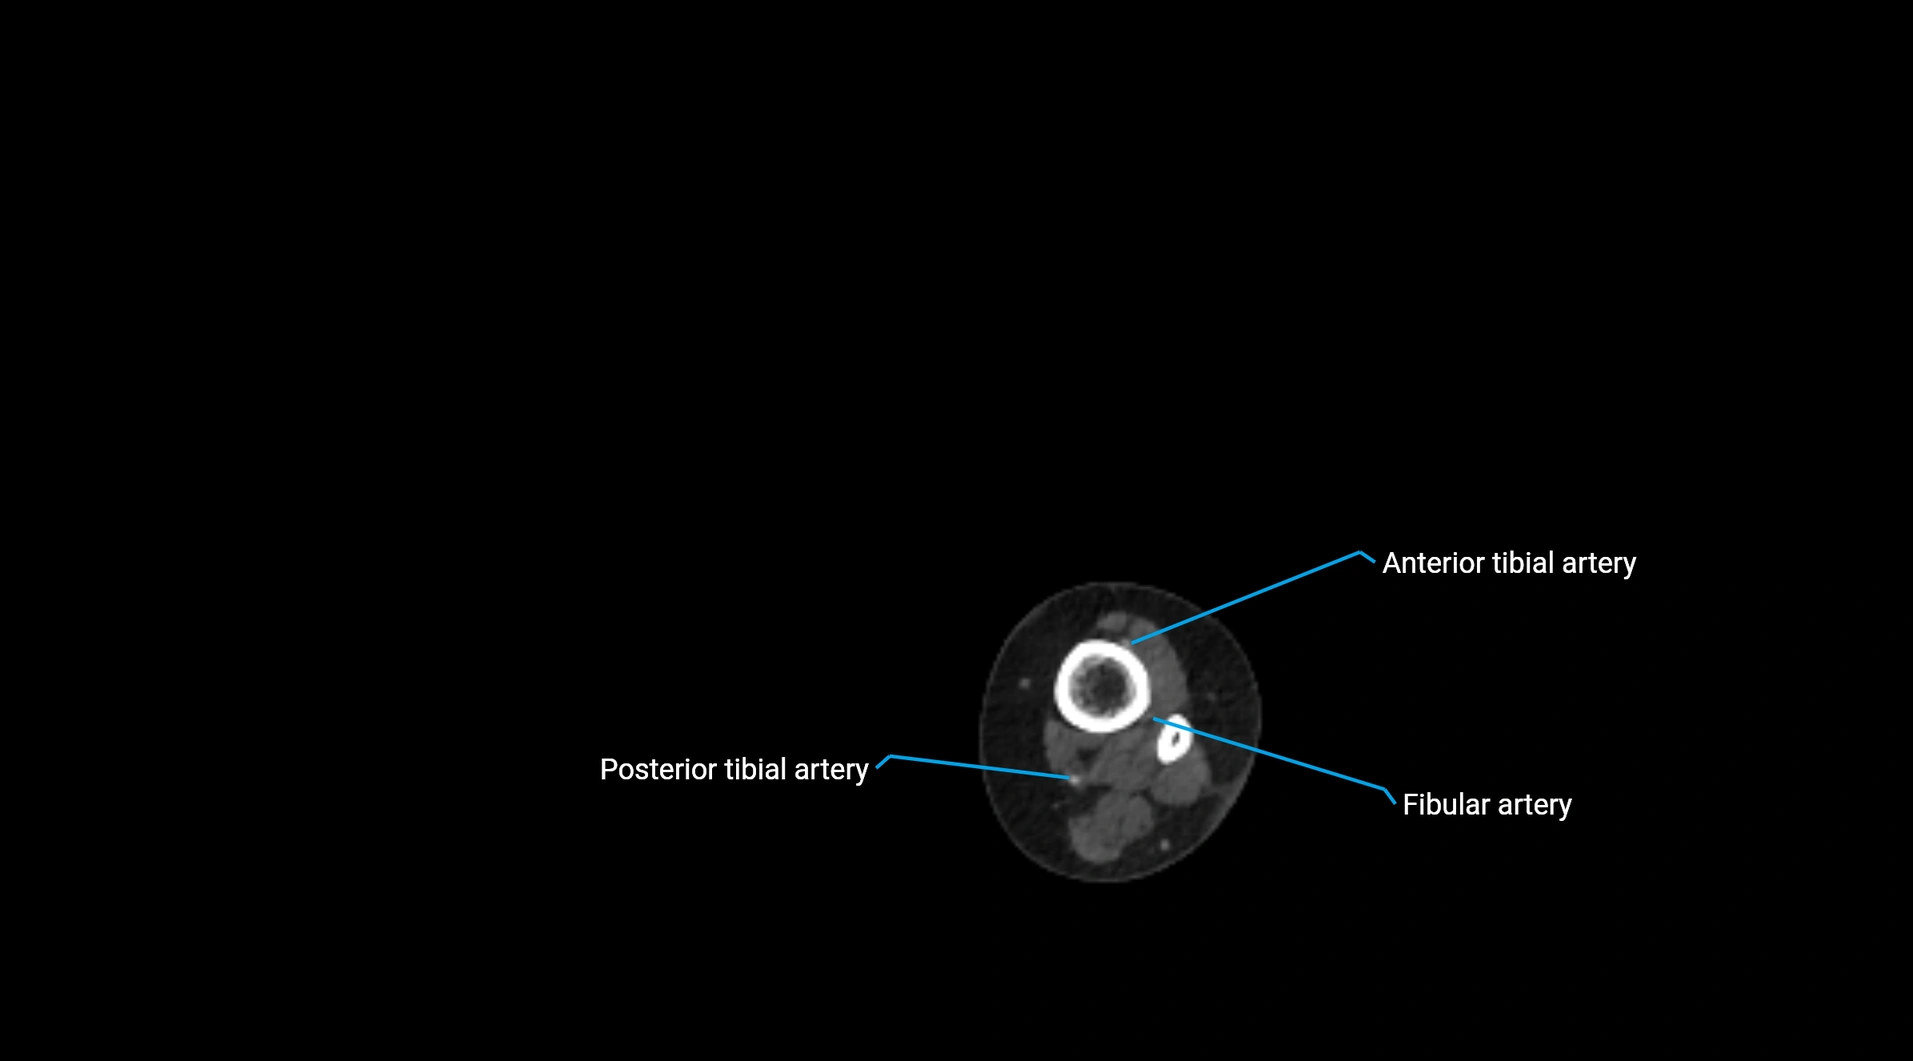

CT images

image